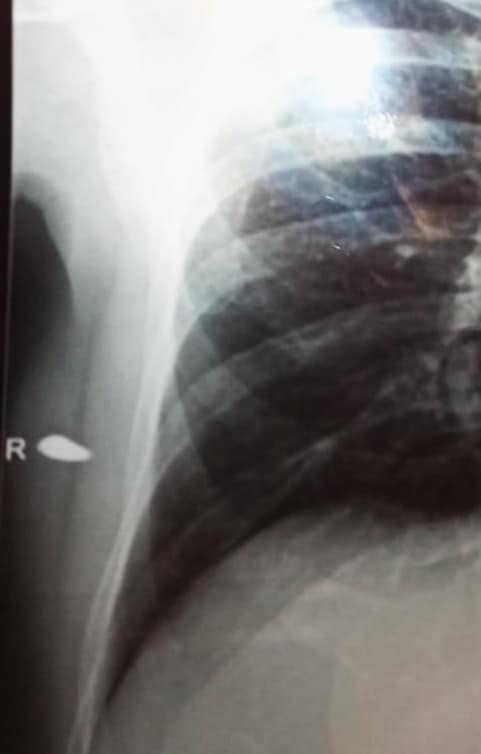

Qarabağ Qarnizonunun ilk hərbi prokuroru, Qarabağ qazisi, müharibədə iki dəfə ağır yaralanmış II qrup əlil, ədliyyə müşaviri Yusif Ağayevin rentgeni yayılıb.

Mia.az xəbər verir ki, sabiq prokuror bu gün də bədənində düşmən mərmisinin qəlpəsini gəzdirir. Rentgendə həmin qəlpə aydın görünür (Aşağıdakı şəkildə: R işarəsinin yanındakı qəlpədir).

Yusif Ağayev prokuror vəzifəsində çalışa-çalışa silaha sarılıb döyüşə atılıb. O, 1992-ci ildə Füzuli, 1993-cü ildə Ağdam istiqamətində ağır yaralanıb. Düşmən mərmisi onun qolunun, kürəyinin bir hissəsini aparıb. Mərmilərdən birinin qalığı – qəlpəsi isə onun bədənində qalıb. Həkimlər sabiq prokurorun həyatına daha böyük təhlükə yarada biləcəyindən ehtiyatlanaraq, qəlpənin çıxarılmasını məsləhət görməyiblər.